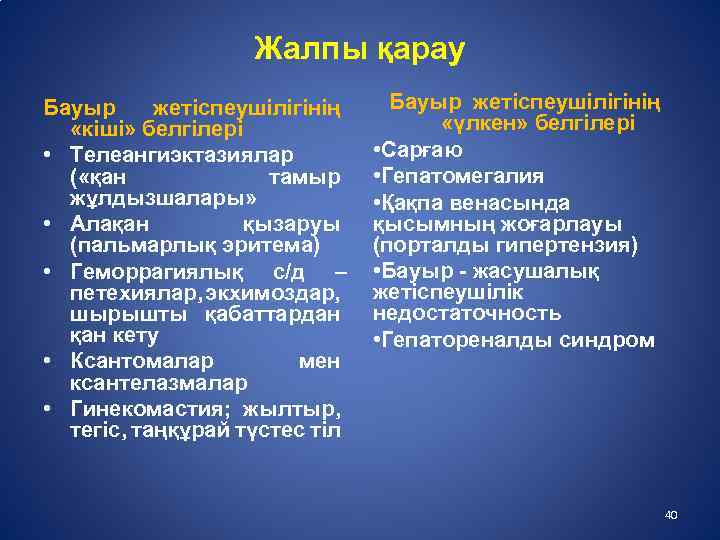

Медицинские термины на фото: визуальное пособие